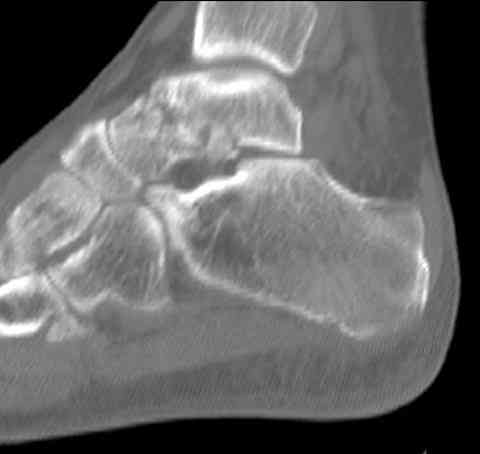

а основании двух видов ренгенограмм невозможно радикально решить о необходимости открытой репозиции или первичного артродеза.

Для оценки состояния нужны дополнительные исследования, например Canale или Broden ренгенограммы и Компьютерная томография.

При переломах тарана всегда имеется риск AVN, а классификация Hawkins поможет разобраться с предполагаемыми осложнениями.

Если в первом типе, когда перелом шейки без смещения, тогда AVN менее 10%, при втором типе когда имеется смещение и вывих тарана в субталарном сочленении меньше 40%, а при типе III когда смещение в голеностопном и субталарном суставах - около 90% и в типе IV, когда происходит полный вывих, риск AVN достигает 100%.

На ренгенограмме не уловил многоскольчатость тарана, чтобы доказать, конечно, можно было исследовать на КТ, потом КТ дает ориентацию фрагментов.

Два фрагмента суставной поверхности тарана можно восстановить боковой компрессией шурупами и дополнительно костная пластика.